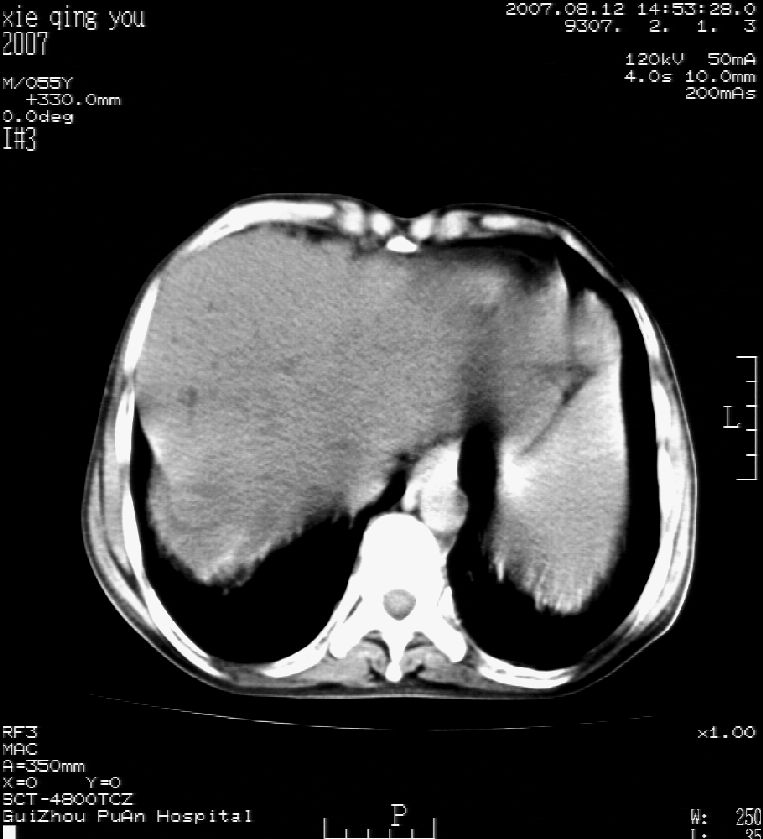

男 55岁  反复上腹痛1年,伴恶心呕吐。2005年做第一次检查后,到外院做b超检查提示肝囊肿,未做任何手术。2006年做过胆总管结石术。骨窗未见异常

2007年8月片

这个病灶很有意思,怎么可能没有了呢?我考虑当时很可能是肝脏脓肿(b超示囊肿是有可能误诊的,因为影像表现都是低回声吗?),现在脓肿吸收了,肝脏萎缩,肝裂增宽了.别的肝叶代偿增大,不过现在左内叶的确有个占位,肝内多发结石,脾脏比以前大,不排除有肝硬化可能.建议增强扫描给于定性!!!!

肝硬化\\脾大,肝左叶肝癌可能性大,建议增强扫描.肝内胆管多发性结石.

1, 肝硬化,脾大;2,肝左叶肝癌可能性大,建议增强扫描.3,肝内胆管多发性结石.

肝硬化、脾大、肝内胆管多发结石。肝左叶低密度占位。建议增强扫描.排除肝癌